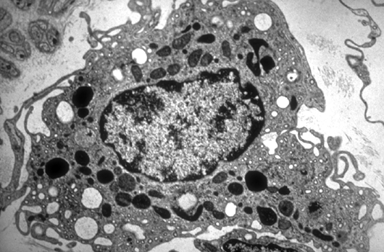

Micro 67. TEM of a macrophage. Macrophages shows numerous cytoplasmic infoldings, vacuoles and residual bodies.